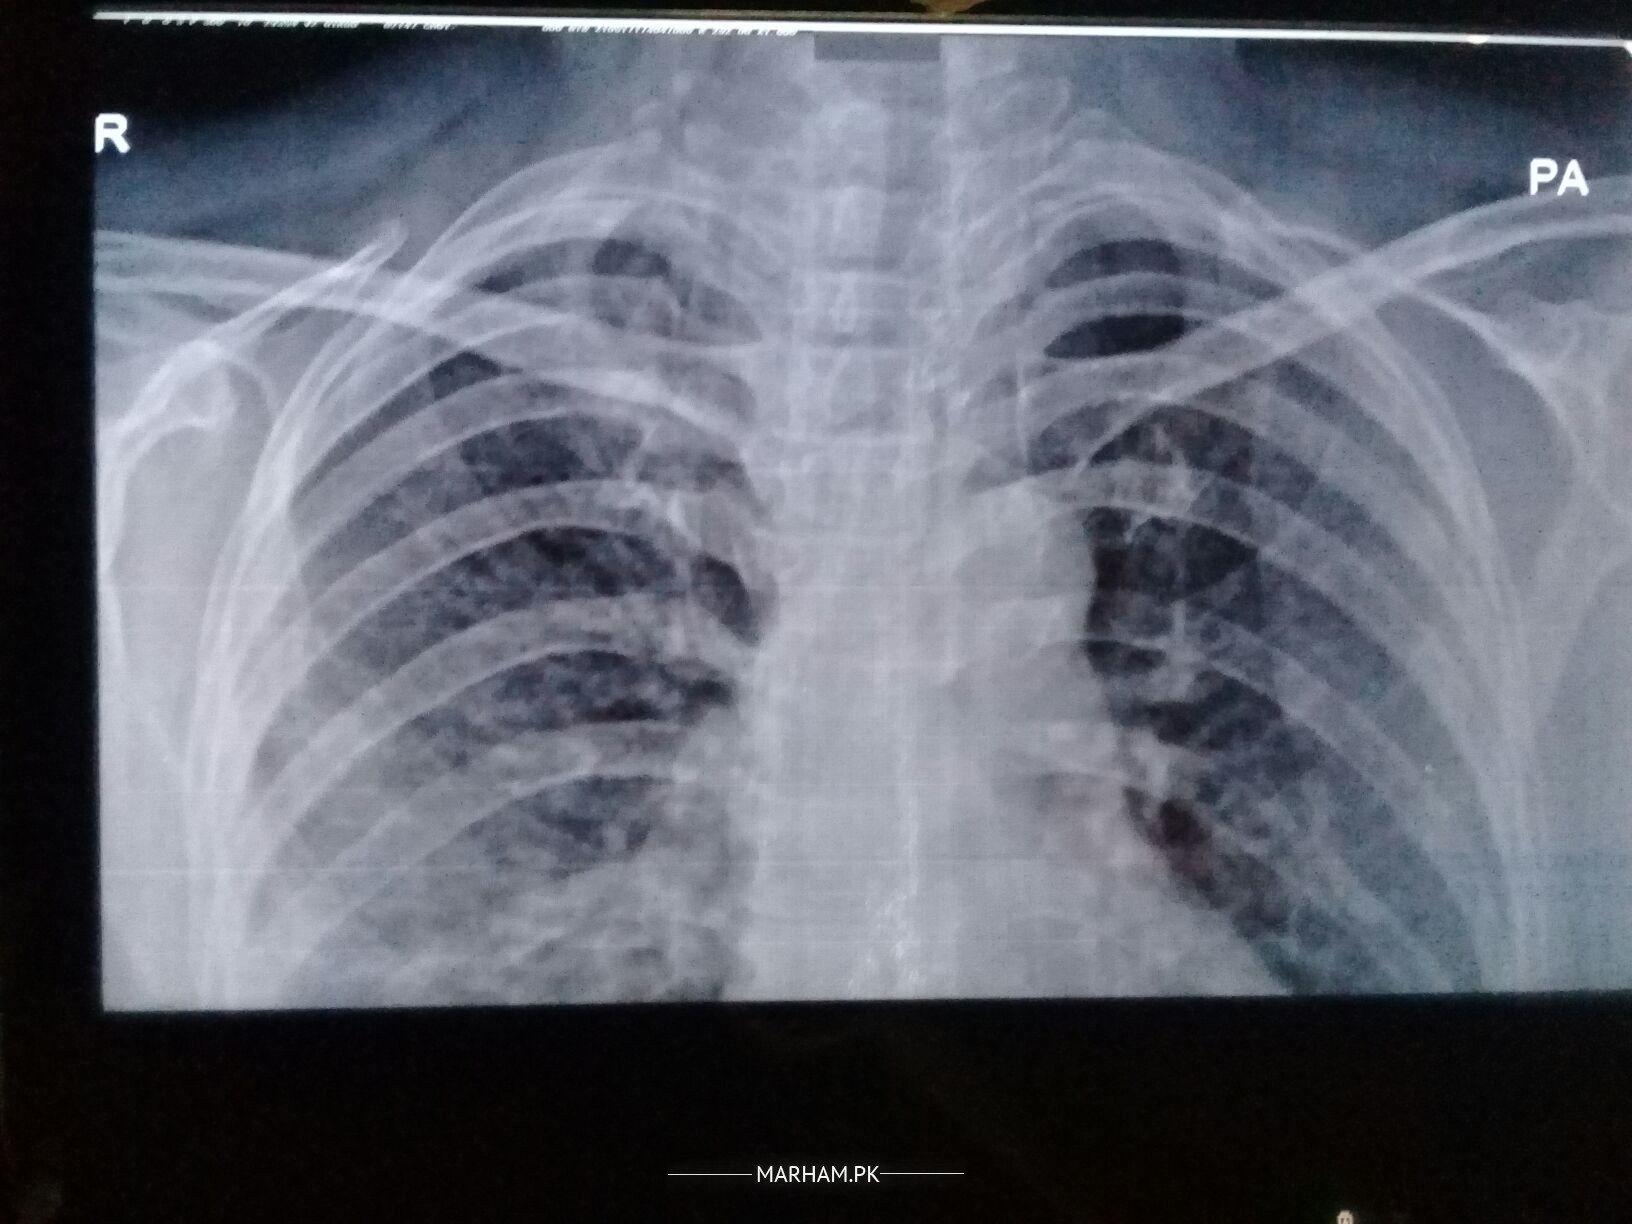

Please check these reports

pehle unhe fever, flue, or body pain rahe hain 10 days k liye but ab inhe cough hai 17 may say ye medicine lay rahe hain medicine prescribed by pulmonologist: 500 mg azithromycin 2 time for 15 days, risek 20 mg 2 time, myteka and softin at night, and nebulization with clenil and atem, syp britanyl 1/2 sp 3 time for 15 days

these symptoms relates to corona as afb is negative,so the prescribed medicine are you should also go for covid test.

Due to current pandemic most likely she is covid positive xrays and crp are also suggestive of covid

Seems to be a covid caseXRay taken on2/5 shows improvement. Duration and dose of Azithromycine needs to be reduced test of the treatment seems ok.